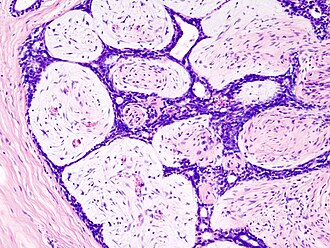

Fibroadenoma. H&E stain. | |

- Abundant (intralobular) stroma - most key feature.

- Stroma is usually:

- White/pale, i.e. myxoid, on H&E (normal stroma is pink).

- May be hyalinized (dark pink) if infarcted.

- Paucicellular - typical.

- Compression of glandular elements - very commonly seen.

- Glandular elements have at least two cell layers - epithelial and myoepithelial.

The sections show a lesion with a pale mildly cellular stroma, and bland glandular elements. Minimal mitotic activity is present (2 mitosis/10 HPF, where 1 HPF ~ 0.2376 mm*mm). The border is well-circumscribed where seen. The lesion was shelled-out.

No cytologic atypia is present. No leaf-like architecture is present. No stromal overgrowth is seen. No calcifications are evident. No large cysts are seen.